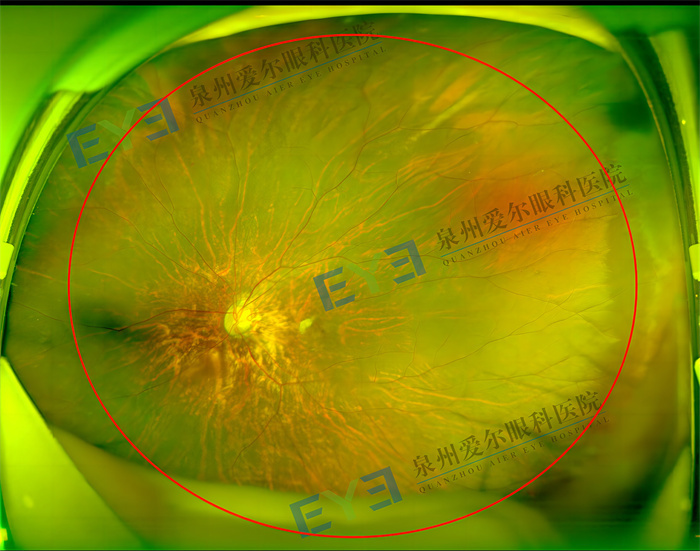

6岁男孩左眼眼轴超26mm多学科专家联合会诊帮其打补丁